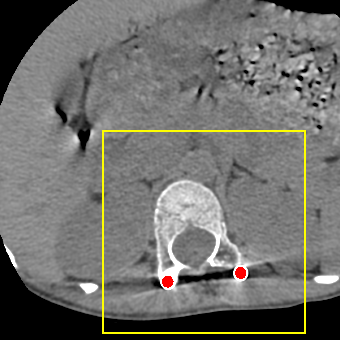

Simulation data. We generate 360,000 cases for training and 2,000 cases for testing based on clean CT images. We first resize CT images to a size of 416416 and use 640 projection angles and 641 rays for imaging geometry to simulate realistic metal artifacts (details are presented in Fig. 2).

Clinical data. We evaluate the proposed method using two clinical datasets. We refer them to DL and CL. DL represents the DeepLesion dataset [13] and CL is a clinical CT scan for a patient with metal rods and screws after spinal fusion. We randomly select 30 slices from DL and 10 slices from CL with more than 100 pixels above 3,000 HU and moderate or severe metal artifacts. The clinical images are resized and processed with the same geometry as the simulation data (see Fig. 2).